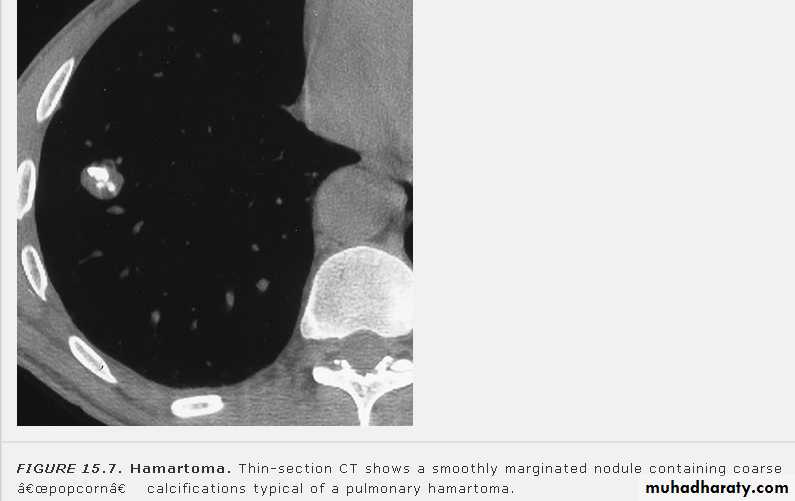

Nodular (coin) lesion in the left upper lung with irregular edge (most probably cancinoma